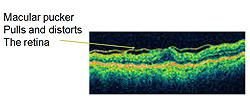

There are other names for this condition, including epiretinal membrane, wrinkled retina, pre-retinal fibrosis, or scar tissue. The condition can result in decreased vision and visual distortion. Straight lines can appear wavy. This is due to the tissue contracting, distorting, and thickening the retina. These changes can best be seen on a cross-sectional image of the retina, which can be obtained by the Retina Health Center specialists using Optical Coherence Tomography (OCT).

OCT delivers high-resolution images to help ophthalmologists determine whether a macular pucker is present. A normal retina appears in image 1, whereas a thickened and distorted retina due to a macular pucker can be seen in image 2. The distorted line at the top of the image represents a macular pucker. This condition is most common in patients over 50. Most of the time, it affects one eye.